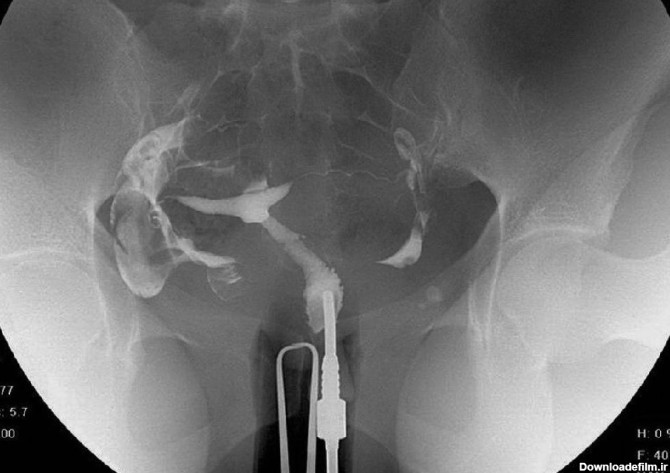

برای بررسی علت تأخیر باروری، باید سلامت اندامهای تولید مثل مورد ارزیابی قرار گیرند؛ یکی از روشهای تشخیصی که برای بررسی رحم و لولههای رحمی درخواست می شود، هیستروگرافی است. با این تست، پزشک از وضعیت داخلی رحم و لوله های رحمی مطلع میگردد و با توجه به نتایج حاصل از تست، در مورد نحوه درمان تصمیم خواهد گرفت. انجام این تست در ارزیابی ناباروری بسیار مهم است.

عکس رنگی رحم با بیهوشی یا بدون درد یکی از خواسته های بانوان است که از حدود شانزده سال پیش توسط دکتر مقدس زاده در مرکز پرتو طب آزما قم در حال انجام است.